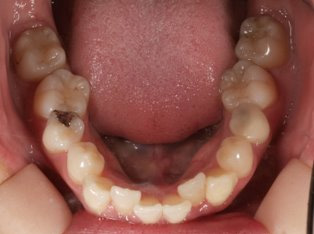

治療前

治療終了前